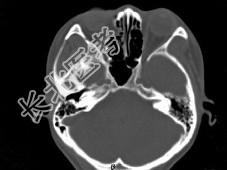

- 单项选择题女,25岁, 因眼部外伤来院就诊,CT如图所示, 最可能的诊断是 ( )

A、右侧颧弓骨折伴筛窦积血

B、右眼眶内侧壁骨折伴筛窦积血

C、右眼眶外侧壁骨折伴筛窦积血

D、右眼眶内外侧壁骨折伴筛窦积血

E、蝶骨骨折伴筛窦积血